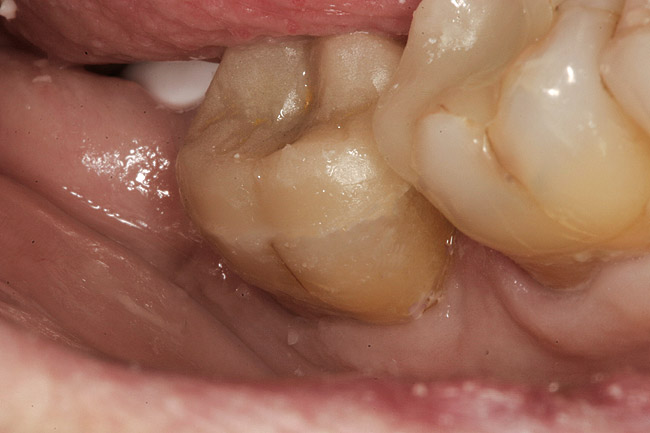

A 70-year-old patient presented with symptoms of a cracked tooth scenario, with intermittent pain upon chewing and thermal sensitivity. The diagnosis was supported through various tests, which determined the lower right second molar had an incomplete fracture that extended from the distal marginal ridge to the mesial marginal ridge. After treatment options were presented, an all-ceramic restoration was decided upon. The tooth was prepared for a nonretentive, adhesively retained all-ceramic restoration ("table top" preparation) (Figure 2 and Figure 3). After the preparation was completed a mild self-etching adhesive was applied to the dentin according to the manufacturer's instruction (Figure 4). There was little concern, if any, of the adhesive reaching the band of exposed enamel. The adhesive was light-polymerized for 5 seconds to secure the layer to the dentin (Figure 5). To eliminate the oxygen-inhibited layer a water-soluble gel was applied to the adhesive and further light-polymerization was completed (Figure 6 and Figure 7). For direct digital scanning cases in which a powdering technique is employed for image capture, it may be more difficult to remove the powder after scanning if the oxygen-inhibited layer is still present.

The next step was to re-prepare the enamel band on the outer perimeter of the tooth with either a carbide finishing bur or a diamond end-cutting bur (Figure 8). This removed any adhesive that inadvertently impregnated the enamel. At this point, the tooth was digitally scanned; if a two-appointment scenario had been utilized then the impression would have been taken and a provisional restoration placed.